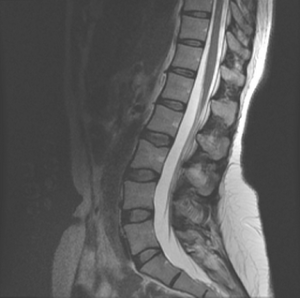

MRI

MRI (magnetic resonance imaging) is another way to make very clear pictures of parts of the spine. The MRI does not use X-rays or radioactive dyes. It can provide clearer pictures of soft tissues such as muscles, cartilage, ligaments, tendons and blood vessels, in addition to bone structure.